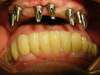

cas n°2 : Péri-implantite